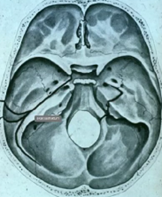

Hematotympanon, benfraktur genom temporalbenet. Som gått in i mellanörat och fyller ut med blod ex. Dålig hörsel. Vad har temporalfrakturen orsakat för effekter, nerver från innerörat till hjärnstam, fascialis, hörsel, balansnerv (övre och undre) – akut yr om någon av dessa är comprimized

Hur ska tänka kring tvärfraktur och längsmedfraktur på temporalbenet?

A

Större risk att nerver som ex fascialis är skadad vid tvärsfraktur (jämfört med längsmed)